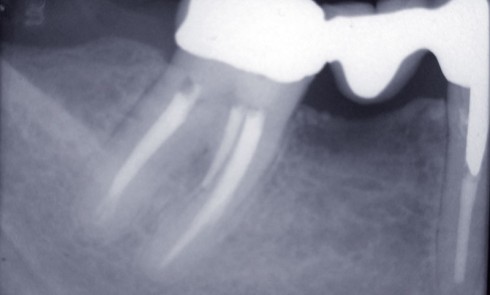

Endodontie

Article réservé à nos abonnés Us et abus des antibiotiques en endodontie (3/3)

Indications prophylactiques (antibioprophylaxie) L’antibiothérapie prophylactique consiste en l’administration d’un antibiotique dans l’objectif de prévenir le développement d’une infection locale, générale...